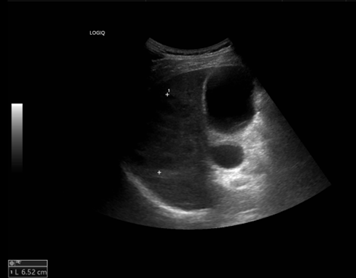

[그림 2] 간우엽에 6.5cm의 저에코성 병변

환자의 임상 증세를 고려하였을 때 화농성 간농양(pyogenic liver abscess)으로 판단되었으며, 경피적 배액술과 경험적 항생제 (3세대 세팔로스포린계열) 치료를 시작하였다. 이후 임상 경과는 점진적으로 호전되었으나, 추적검사로 상태 안정된 후 조영제를 사용한 역동정 조영증강 CT 검사에서 총담관 확장 소견이 동반되어 [그림3] 추가적인 원인 평가를 시행하였다.